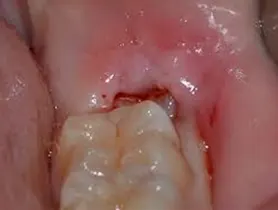

É muito comum haver dor na região do dente do siso quando ele está nascendo. A gengiva pode ficar um pouco inflamada, apresentando dor, vermelhidão e sensação de calor. Para aliviar a dor devemos manter a região muito bem higienizada, recorrer ao uso de enxaguante bucal próprio para estes casos e, se necessário, usar analgésicos. Em poucos dias os sintomas desaparecem. Se o dente estiver icluso ou parcialmente incluso, deve procurar nossa clínica para uma orientação e diagnóstico do caso.

ASPECTO DE SISO INCLUSO: